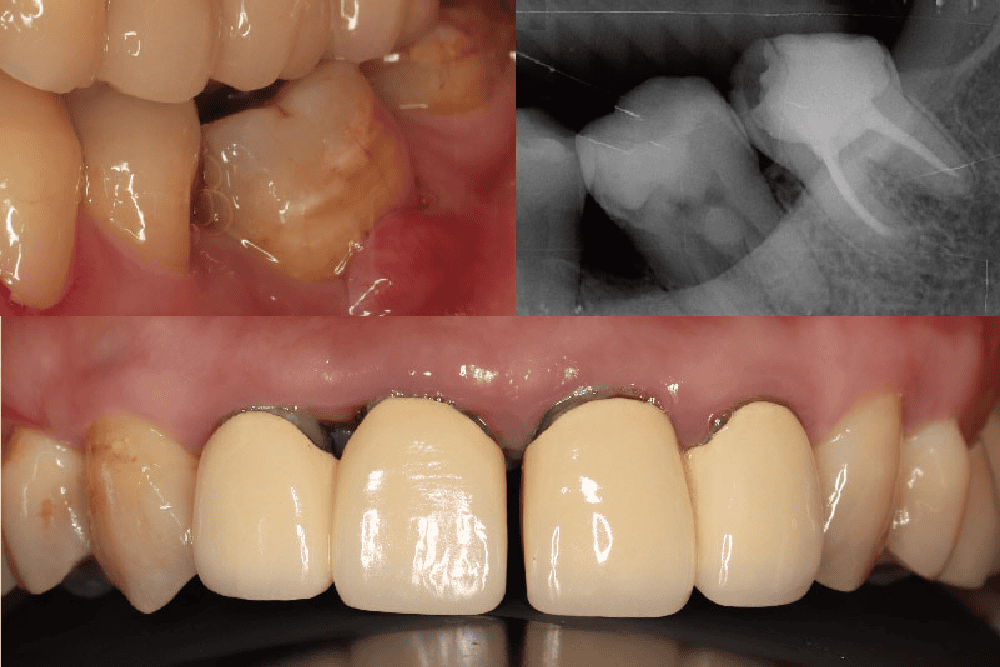

當代楊新牙醫診所牙周病暨植牙專科醫師葉立維表示,經過環口式全口X 光片和牙神經活性檢查後,發現患者左邊下面臼齒曾有大範圍填補,同時牙神經也沒有活性反應,顯示這顆牙齒同時有牙髓和牙周的問題;再加上此區域的齒槽骨已經流失 50%以上,診斷為全口中度至嚴重牙周病,完整檢查與精確診斷後擬定了全口治療計畫。

經過牙周特別檢查,加上測量囊袋深度和 X 光片上顯示齒槽骨流失的狀況,可以估計整體或單獨牙齒的預後。醫師表示,患者的治療計畫包括顯微根管治療後,用覆蓋式全瓷嵌體修復左下大臼齒的牙髓和牙周問題、全口牙周病治療、拆除前牙區不密合的假牙並且重建,同時針對右下缺牙區域因拔牙很久導致牙齦萎縮,先以游離牙齦移植術增寬牙齦後,再進行人工植牙療程。

新聞照來源:當代楊新牙醫診所